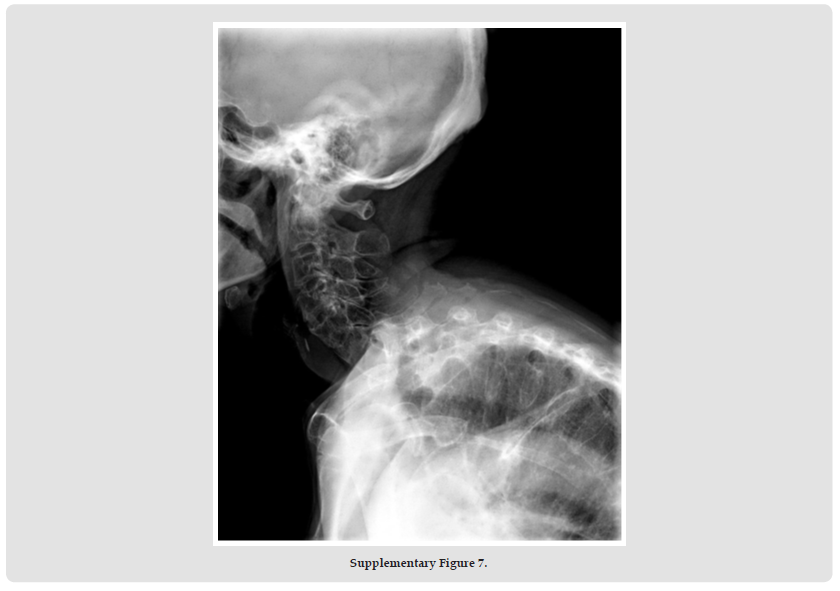

Psoriatic arthritis (PsA), a systemic autoimmune disease, manifests with remarkable clinical heterogeneity [1]. While axial involvement and peripheral joint destruction are well documented, the coexistence of severe spinal kyphosis and Mutilans-type arthropathy remains exceptionally rare. We present a diagnostically challenging case with concurrent progressive spinal deformity and osteolytic features of Mutilans [2]. This case report describes the complex clinical presentation of a rare psoriatic arthritis (PsA) patient with severe kyphosis and mutilating arthritis. A 69-year-old woman with a 50- year history of psoriasis developed worsening skin symptoms and joint pain in 2019. She was treated with cyclosporine, ezicizumab and secukinumab, which resulted in partial relief of skin symptoms but progressive joint destruction. Over the past two years, he had developed a complex sagittal and coronal spinal deformity (thoracolumbar kyphosis with scoliosis), accompanied by characteristic “telescopic” phalangolysis and ulnar deviation of the right hand. His serum markers (RF, anti-CCP, etc.) were normal. Imaging showed the coexistence of heterotopic ossification and osteolysis, consistent with the diagnosis of residual PsA combined with spinal PsA. The clinical significance of this case is that it highlights three key issues. Firstly, rapidly progressive spinal lesions can occur in the absence of a typical serological marker (negative HLA-B27); secondly, biological agents can cause separation of skin and joint effects.

Third, mechanical stress may accelerate the progression of spinal deformity in susceptible individuals. This suggests that dynamic monitoring of the spine in PsA patients should be intensified, especially in patients with long-term good skin control but new axial symptoms, and the evaluation strategy should be adjusted. Future research needs to further explore the mechanical-inflammatory interaction mechanism and establish precise treatment pathways for different clinical phenotypes. This case provides an important clinical demonstration to recognise the heterogeneity of PsA and the complexity of treatment (Supplementary Figures 1-11).